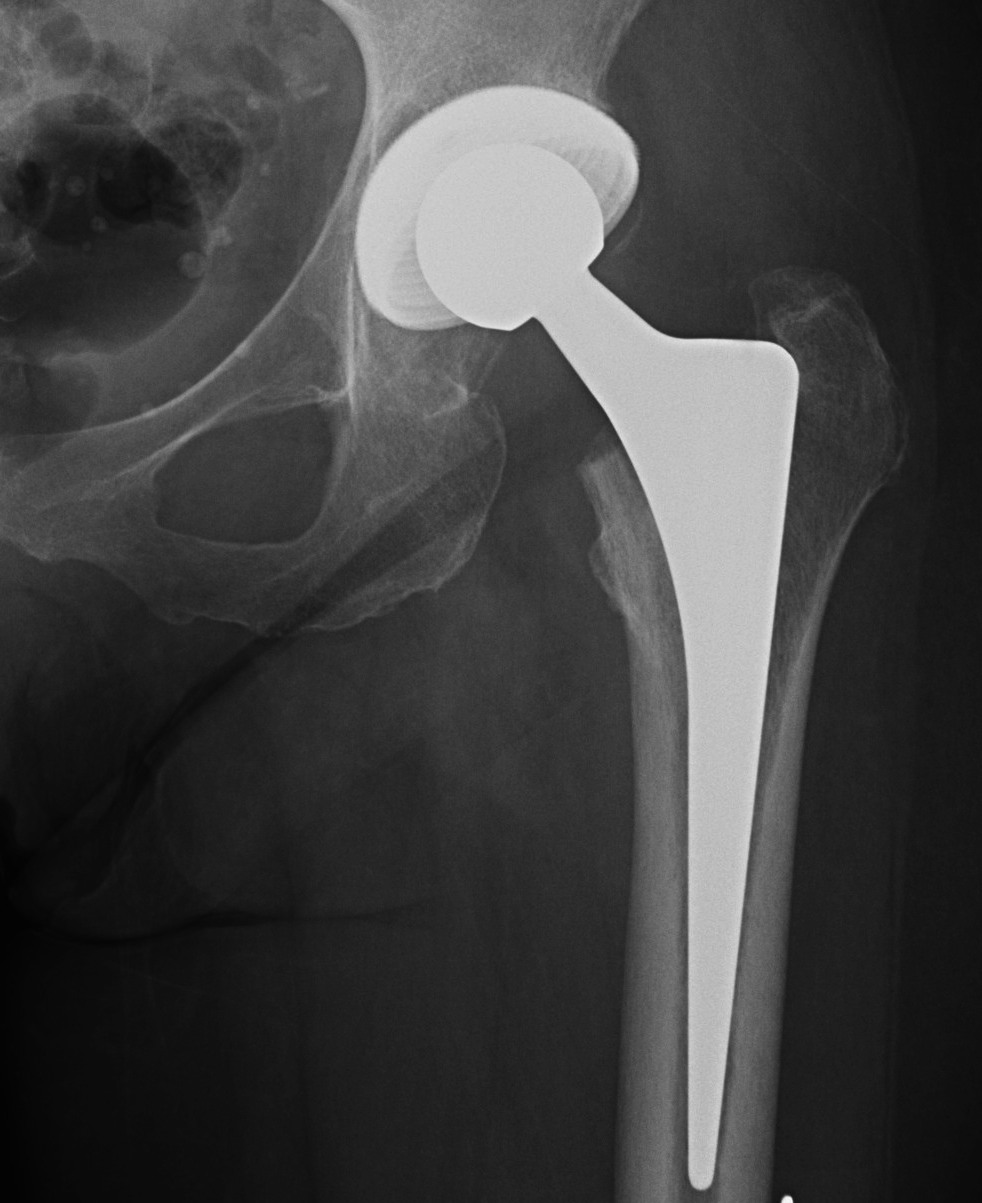

Indications

Disabling hip pain

Severe functional impairment

Failure non operative management